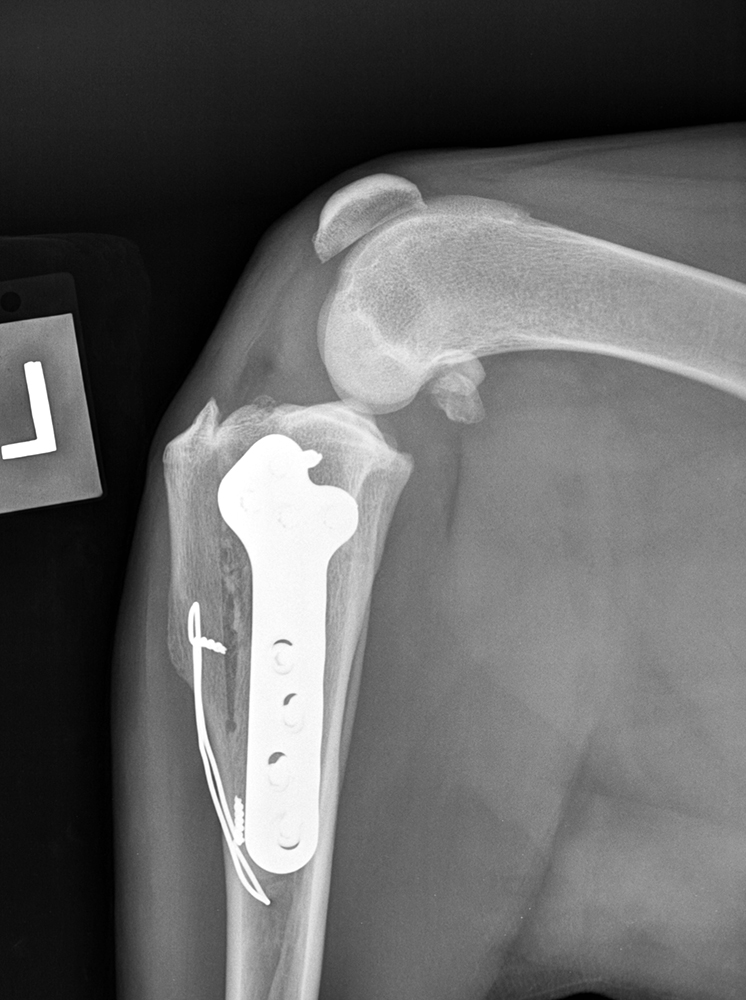

Médiolatérale